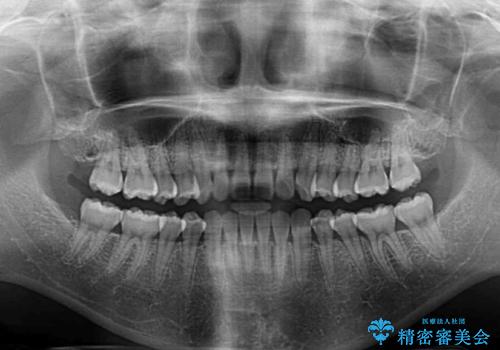

1日22時間の装着時間をしっかり守ってくださったので、1年程度で治療を終えることができました。

1セットのマウスピースで概ね治療を終えたのですが、前歯僅かな叢生が残ったため、2セット目のマウスピースで仕上げました。

気にしていた口元の印象が改善され、患者様には大変満足していただきました。